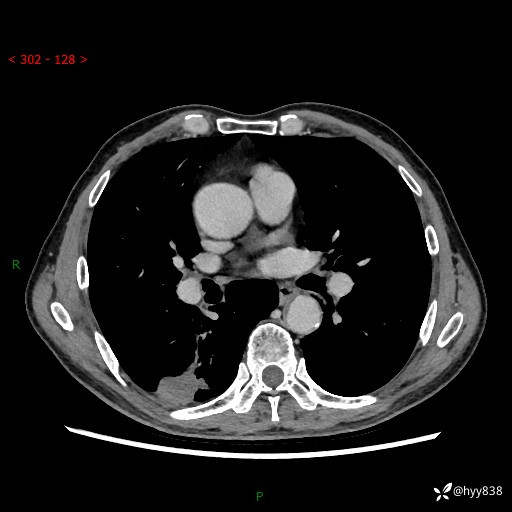

简要病史:患者3天前于我院常规体检时行胸部CT提示“右下肺结节35mm*24mm”,自觉无发热、咳嗽、咳痰,无胸痛、咯血、气促加重,无声嘶、吞咽困难,无乏力、盗汗、体重减轻等不适。为求进一步诊治,入我院求诊,门诊以“右下肺结节待查”收入我科。患者3天前于我院常规体检时行胸部CT提示“右下肺结节35mm*24mm”,自觉无发热、咳嗽、咳痰,无胸痛、咯血、气促加重,无声嘶、吞咽困难,无乏力、盗汗、体重减轻等不适。为求进一步诊治,入我院求诊,门诊以“右下肺结节待查”收入我科。 起病以来,患者精神、食欲、睡眠可,体力稍差,大小便正常,体重无明显变化。

辅助检查:CT

胸部CT平扫